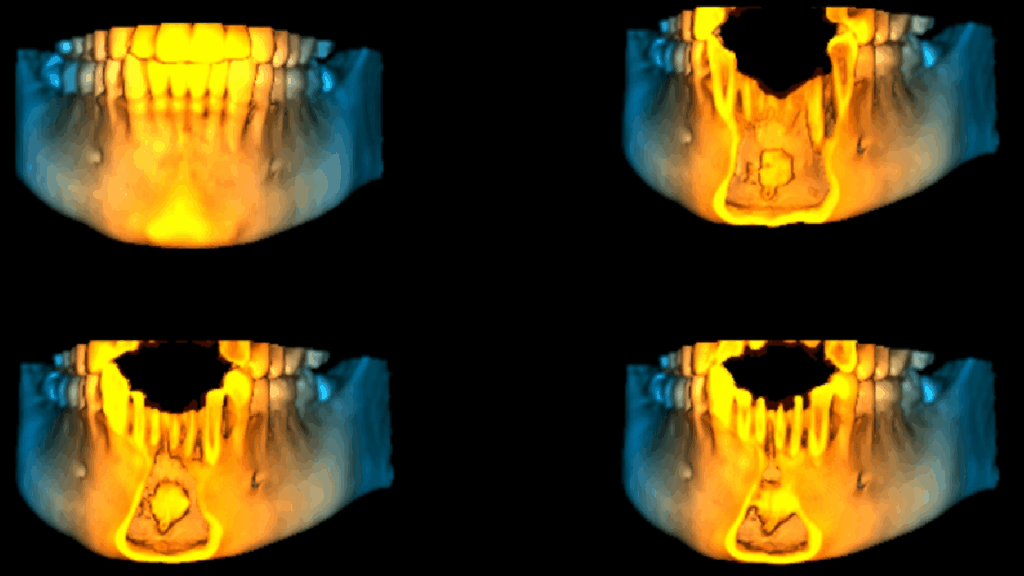

En las reconstrucciones 3D se representa Mesiodens. (Figura 4).

RECONSTRUCCIÓN 3D

- Mesiodens.